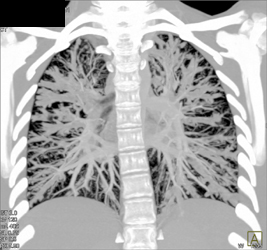

Cystic Fibrosis